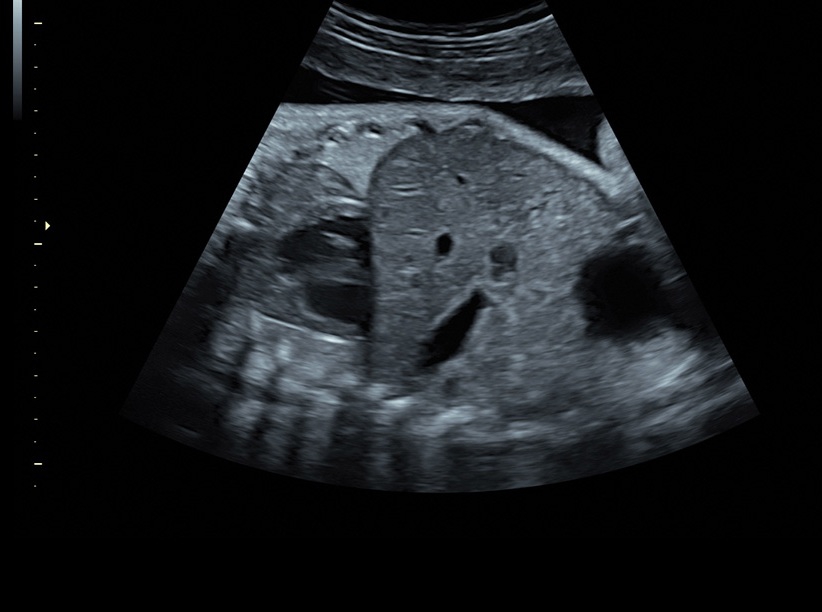

Ультразвуковая платформа Voluson S8 представляет собой оборудование экспертного класса с передовыми возможностями и высоким уровнем автоматизации процессов. Она позволяет проводить сканирование в режимах 2D, 3D и 4D с высоким качеством изображений.

Аппарат Voluson S8 базируется на надежной платформе VCA, которая имеет множество положительных отзывов. Она обладает высококонтрастной технологией объемной реконструкции, обеспечивая качественное воспроизведение изображений. Информация выводится на широкоформатный цветной монитор размером 23 дюйма для убедительной демонстрации плода будущим родителям и облегчения работы врача.

• Высокое качество изображений: Voluson S8 обеспечивает высококачественные изображения, позволяющие детально оценить состояние плода и обнаружить возможные патологии.

• Технология автоматической фетометрии в 2D режиме (SonoBiometry): Эта технология позволяет автоматически измерять бипариетальный размер, окружность головы, окружность живота, длину бедра и плеча плода, обеспечивая точные и надежные измерения.

• Технология SonoRenderlive: Эта технология облегчает получение 3D/4D изображений путем автоматического изменения положения плоскости визуализации в зависимости от движений плода. Она позволяет получить реалистичные и объемные изображения, что полезно для демонстрации плода будущим родителям и для дополнительного анализа.